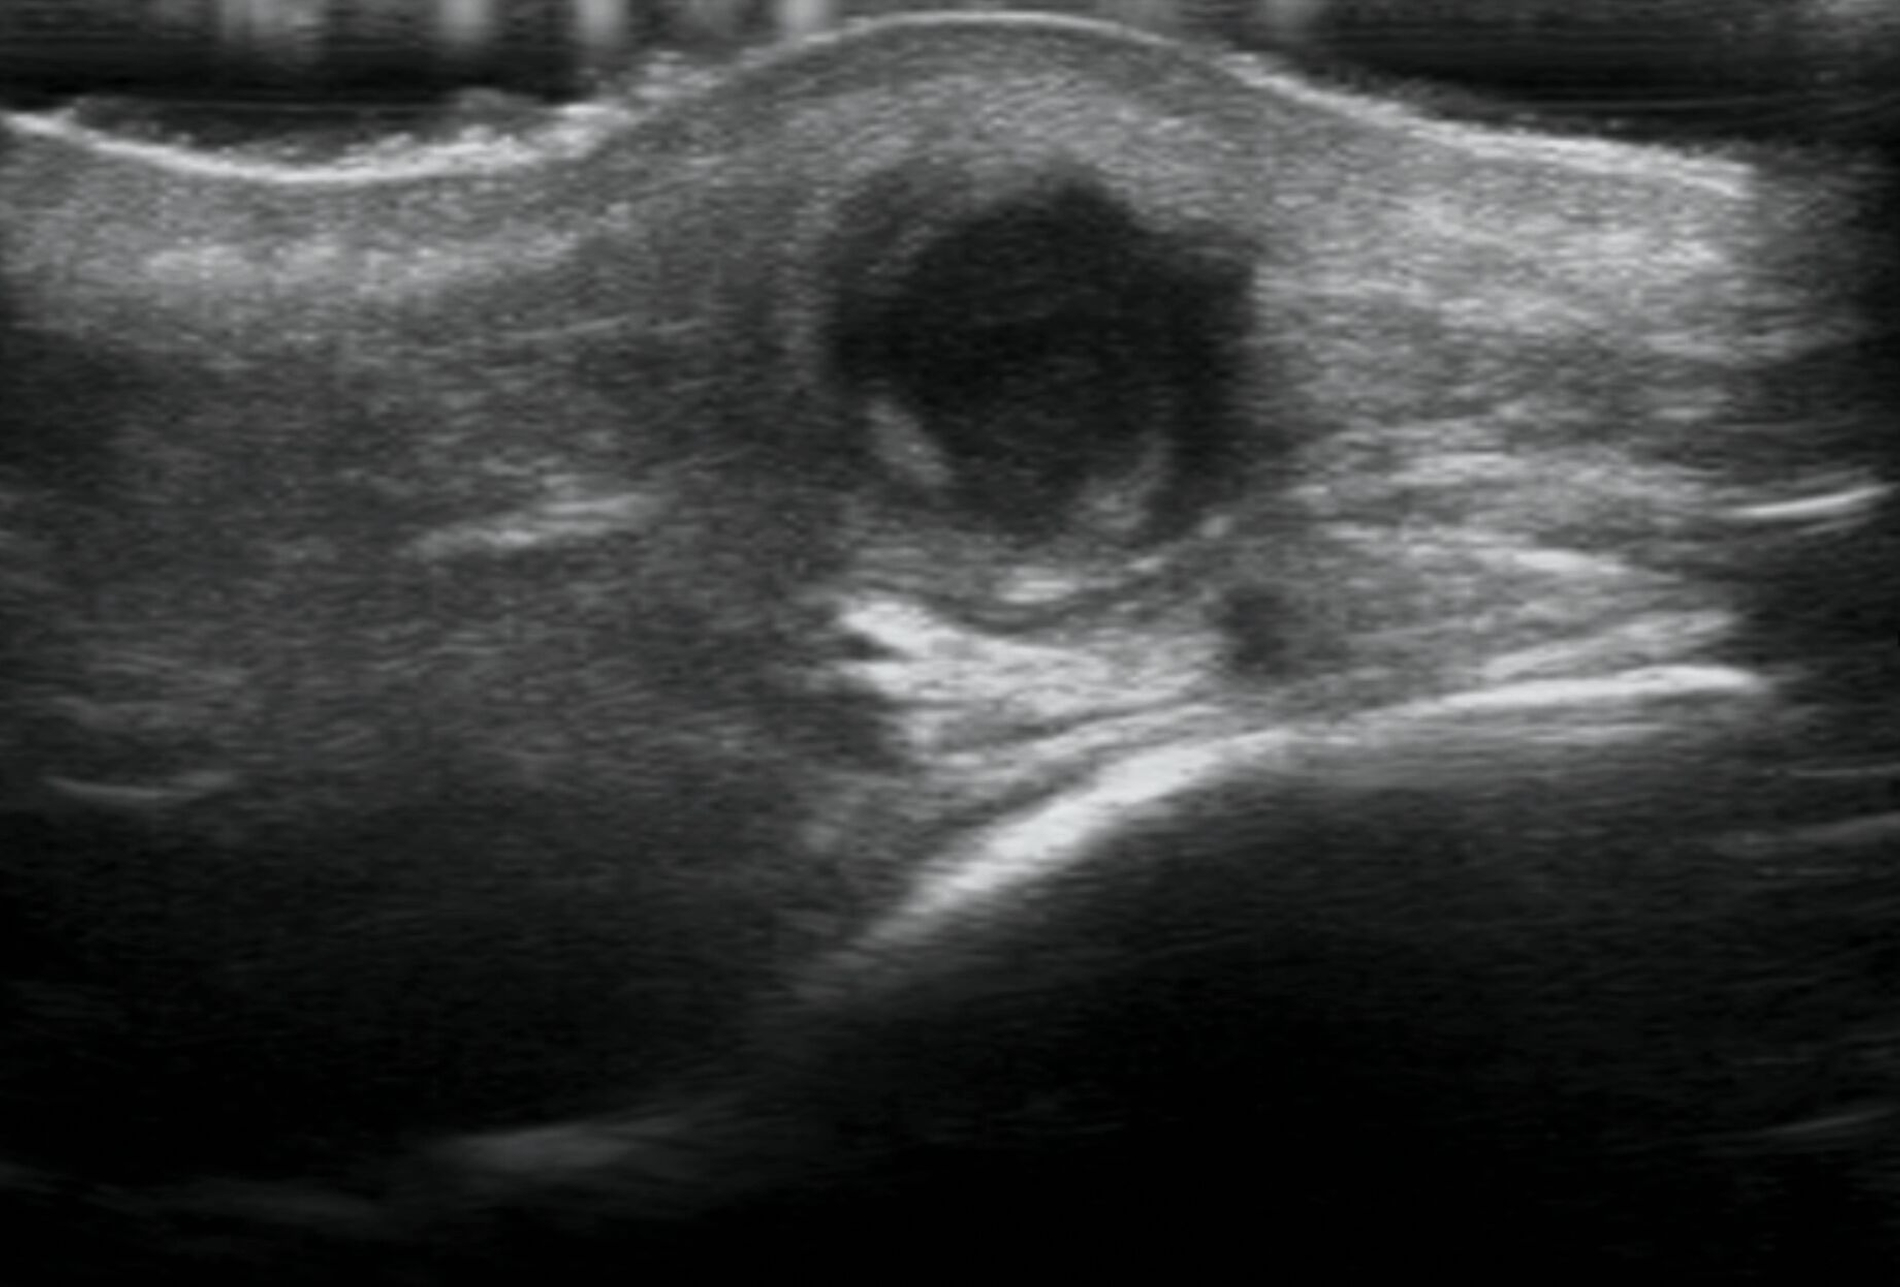

Es präsentierte sich ein Patient in gutem Allgemein- und Ernährungszustand. Relevante Vorerkrankungen ließen sich nicht eruieren. Klinisch zeigte sich eine derb palpable Schwellung der linken Wange mit Adhärenz nach enoral (Abbildung 1). Sonografisch ließ sich ein echoarmes Grundmuster mit Binnenreflexen und unregelmäßiger Wandstruktur darstellen (Abbildung 2). In der anschließenden radiologischen Diagnostik zeigte sich ein periapikal osteolytisch veränderter Knochen im Bereich des Zahnes 37 (Abbildung 3). Nebenbefundlich präsentierte sich eine beginnende apikale Aufhellung an der mesialen Wurzel des Zahnes 36 mit Verdacht auf inkomplette Wurzelkanalfüllung. Die erweiterte Diagnostik mittels Digitaler Volumentomografie offenbarte eine Osteolyse der vestibulären Lamelle in Regio 37 (Abbildung 4). In Zusammenschau der Befunde wurde die Verdachtsdiagnose einer chronisch entzündlichen Veränderung nach Partsch gestellt.